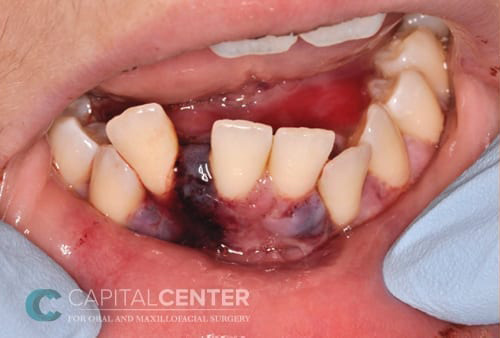

Injuries To The Teeth & Surrounding Dental Structures

Isolated injuries to teeth are quite common and may require the expertise of various dental specialists. Oral & Maxillofacial Surgeons usually are involved in treating fractures in the supporting bone or in replanting teeth that have been displaced or knocked out. These types of injuries are treated by one of a number of forms of splinting (stabilizing by wiring or bonding teeth together). If a tooth is knocked out, it should be placed in salt water or milk. The sooner the tooth is re-inserted into the dental socket, the better chance it will survive. Therefore, the patient should see a dentist or oral surgeon as soon as possible. Never attempt to wipe the tooth off, since remnants of the ligament that hold the tooth in the jaw are attached and are vital to the success of replanting the tooth. Other dental specialists may be called upon such as endodontists, who may be asked to perform root canal therapy, and/or restorative dentists who may need to repair or rebuild fractured teeth. In the event that injured teeth cannot be saved or repaired, dental implants are often now utilized as replacements for missing teeth.